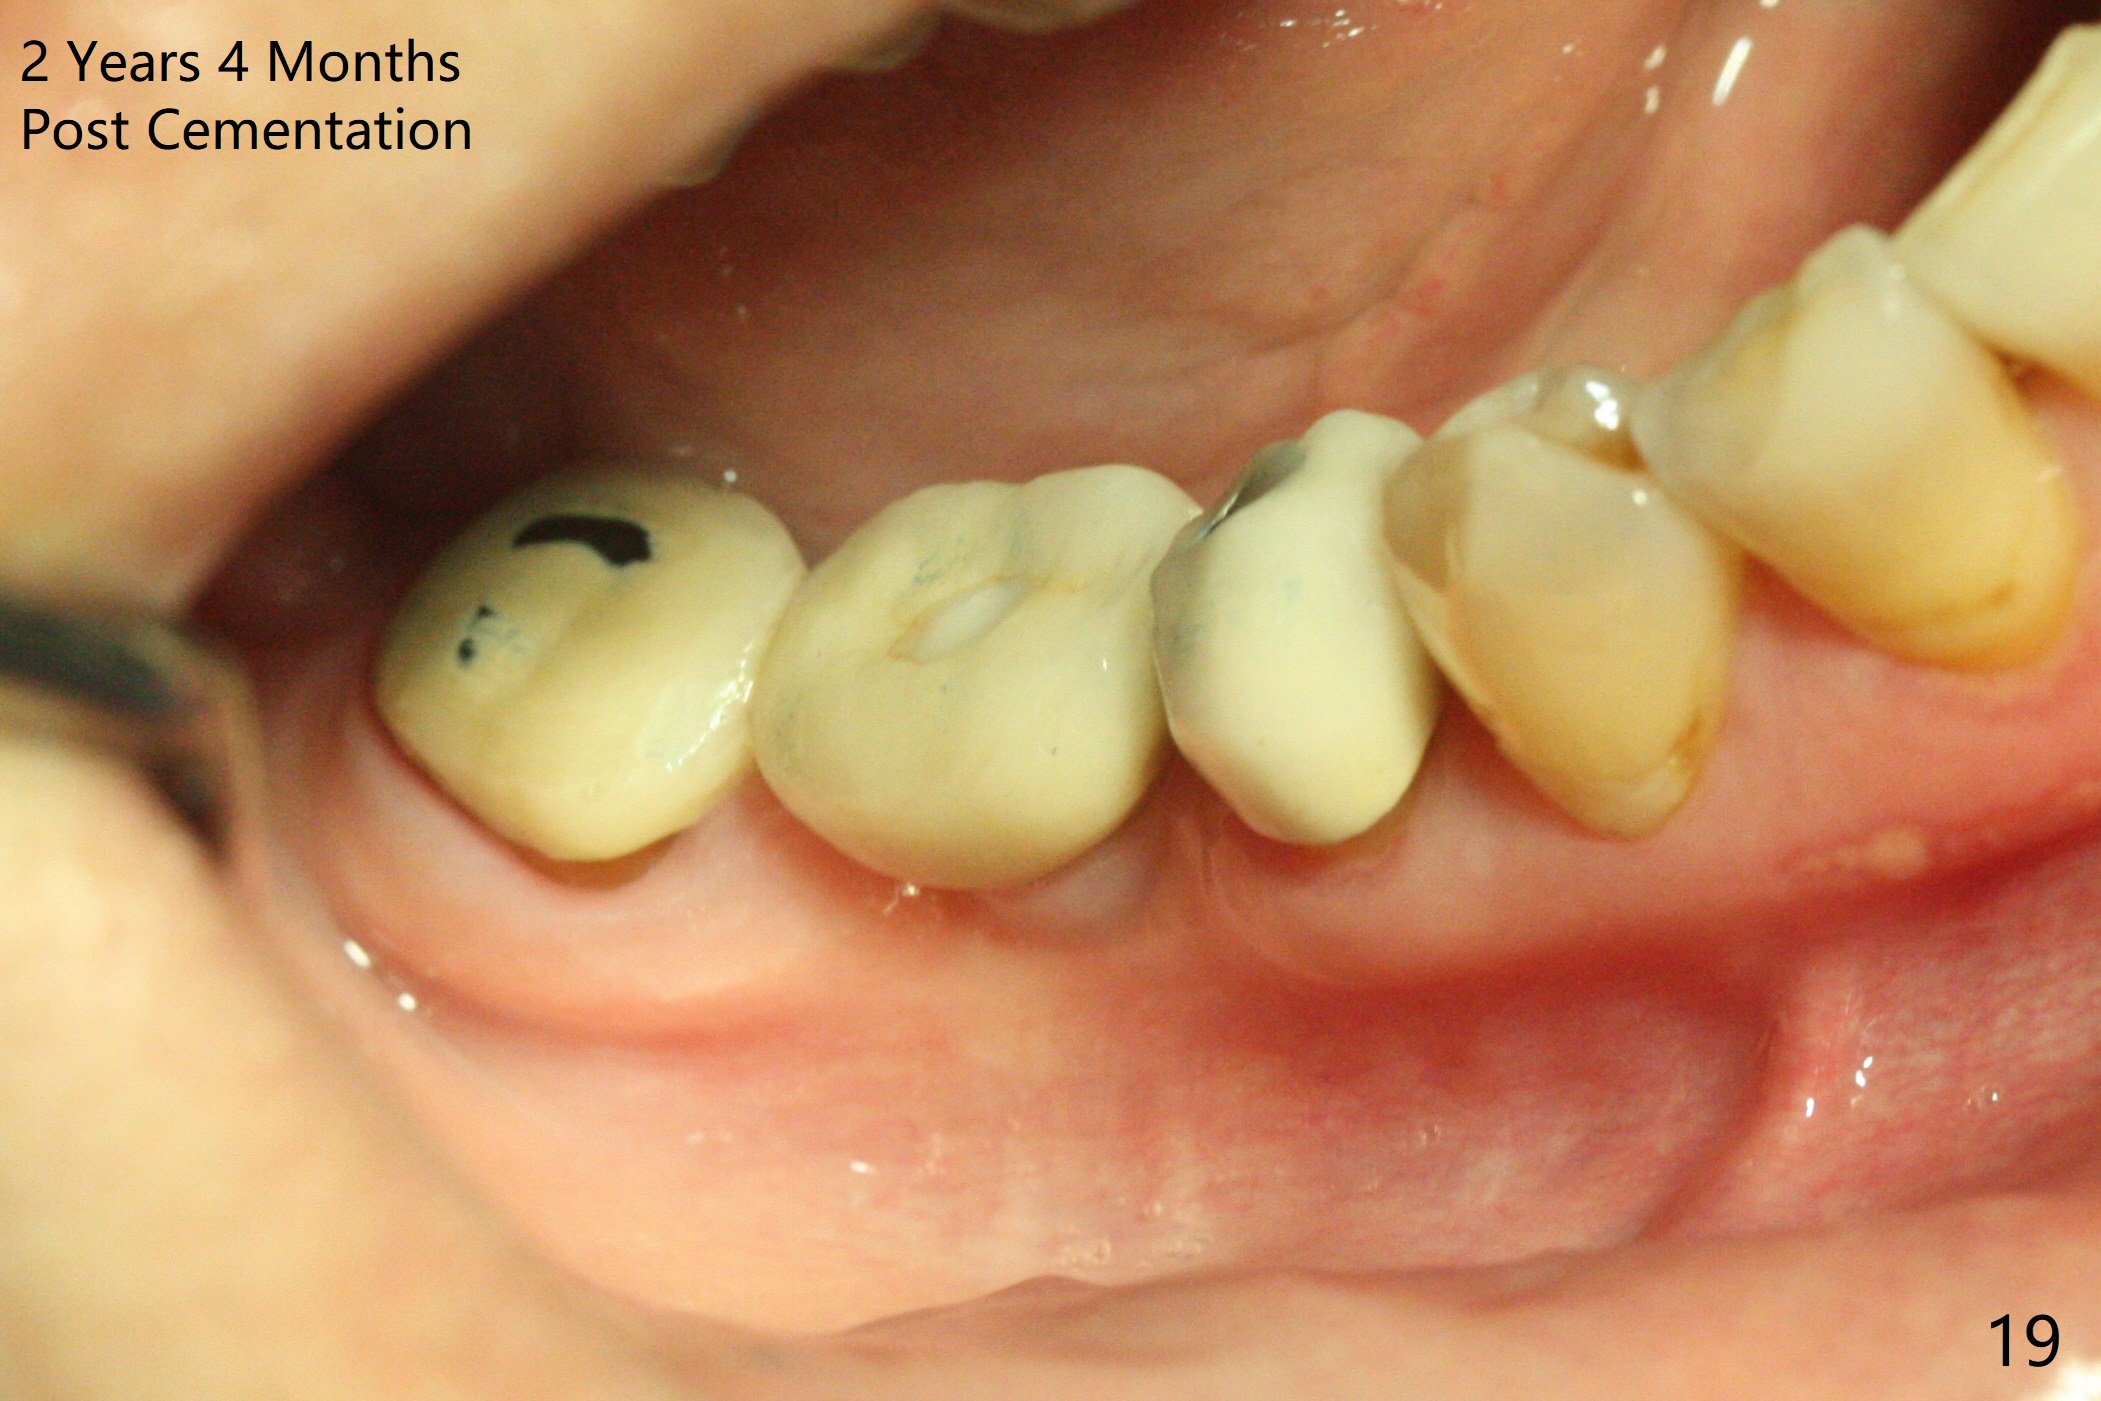

Splinted provisional is fabricated #30 and 31 one month postop. The patient returns for final restoration (single units) nearly 4 months postop (Fig.11). Since the margin is subgingival, a screw type crown is fabricated for #30 (Fig.12). The buccal gingiva looks convex after healing cap removal (Fig.13, as compared to Fig.4 (concave)). PA is taken immediately post tightening and cementation (Fig.14, 5 months postop). It appears that new bone has grown between the most coronal threads (arrows). The bone density immediately around the implant appears to increase 1.5 years post cementation (Fig.15,16). She returns because of failure of 18-20 bridge (implants will be placed at 18/19). The implant at #30 is in fact not placed deep enough; the coronal threads seem to be exposed, although there is no periimplantitis (Fig.17 CT). The tooth #31 is symptomatic; the mesial canal is missing (Fig.18 M, <). The gingiva around the crowns at #30 and 31 remains healthy 2 years 4 months post cementation (Fig.19). Metal exposure of the crown at #31 is intentional. Occlusal reduction is done to alleviate periapical re-infection (Fig.18).